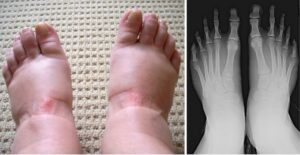

Take a look at this Chinese foot map that helps worldwide in therapies for foot pain.